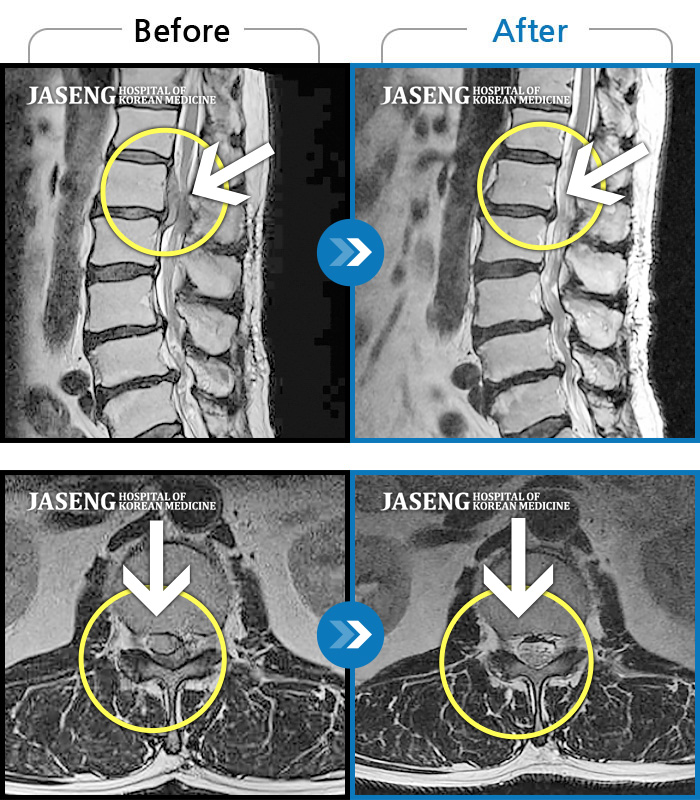

허리디스크

수원 · 김태성 원장

우측 허리 통증과 우측 다리 방사통으로 활동하기 힘든 상태

촬영시기

2021.02.03 ~ 2021.07.09

2022.03.25